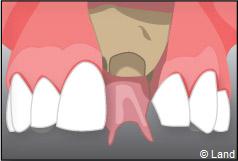

Exemple d’un implant unitaire pour remplacer une dent antérieure manquante.

Le chirurgien-dentiste après une anesthésie locale pratique une incision, puis il décolle la gencive pour accéder à l’os alvéolaire.

L’implant est placé dans l’os le plus souvent par vissage et doit avoir une liaison forte avec l’os. Le praticien replace alors la gencive et pose des points de suture.